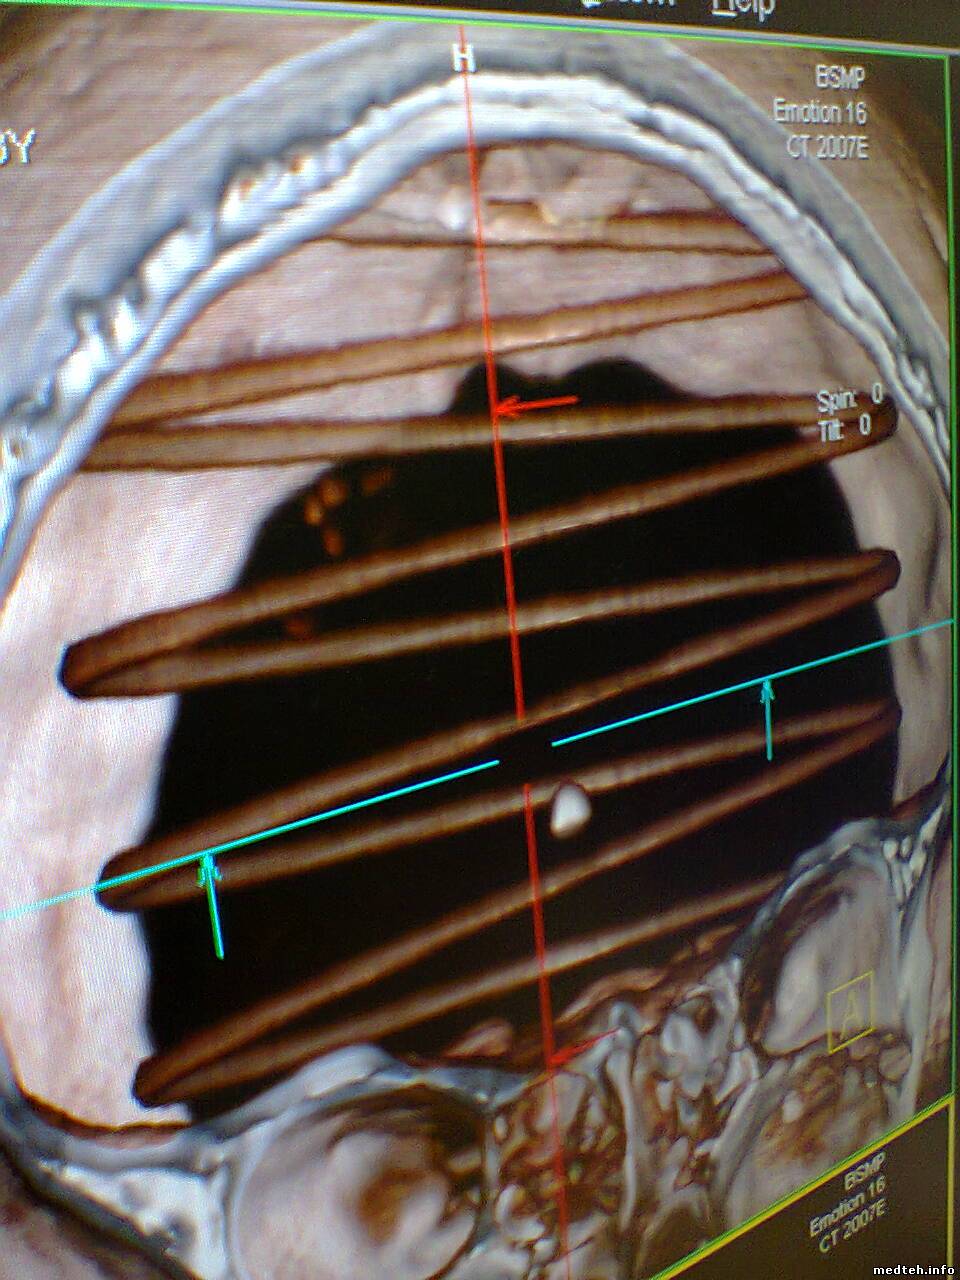

Здравствуйте, появился спиральный артефакт на изображениях, который исчезает примерно на день если провести калибровку по воздуху, думал что дело в модуле датчиков но тест defective channels не показывает ошибок. Что-нибудь кроме датчиков может давать такое изображение? Есть вероятность что детектор как-бы отпаивается? Можно ли тогда запаять его обратно?

1233008.jpg (169.7 Kb) · 7047881.jpg (198.7 Kb) · 0284259.jpg (186.5 Kb) · 0243983.jpg (196.8 Kb) · 3573226.jpg (195.6 Kb)